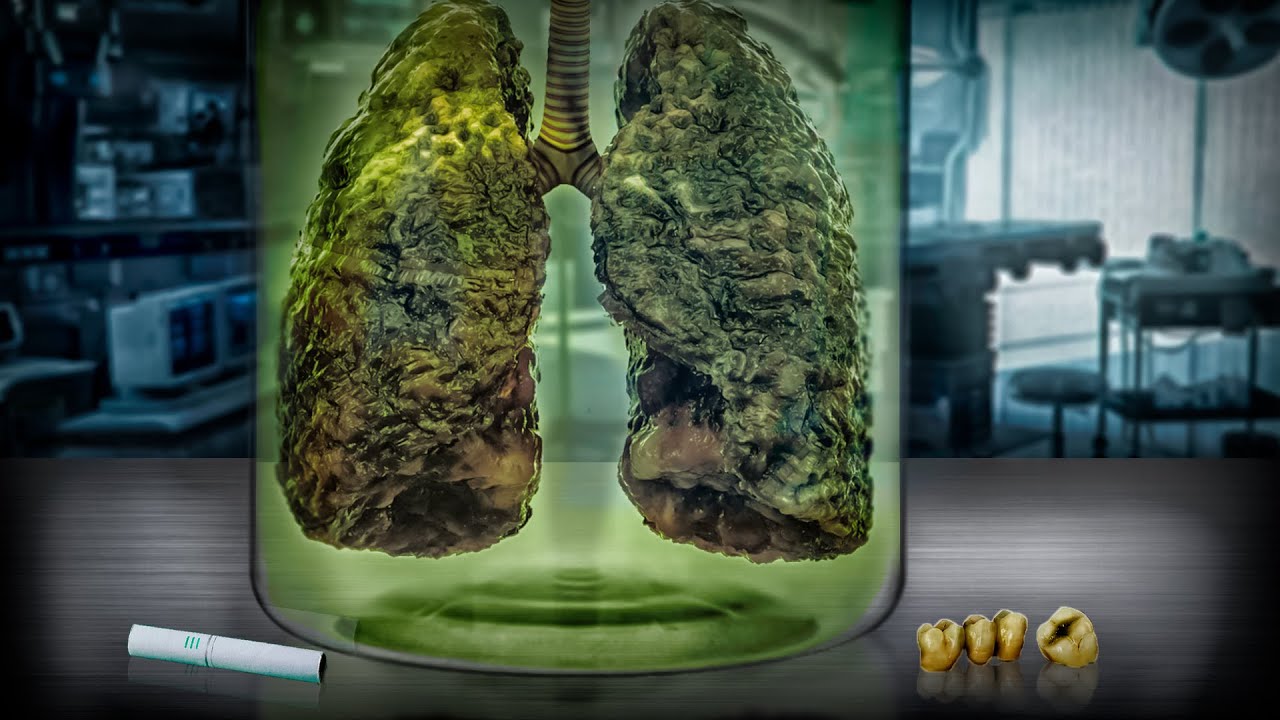

Здоровый образ жизни: Влияние курения

Раздел: Моменты озарения